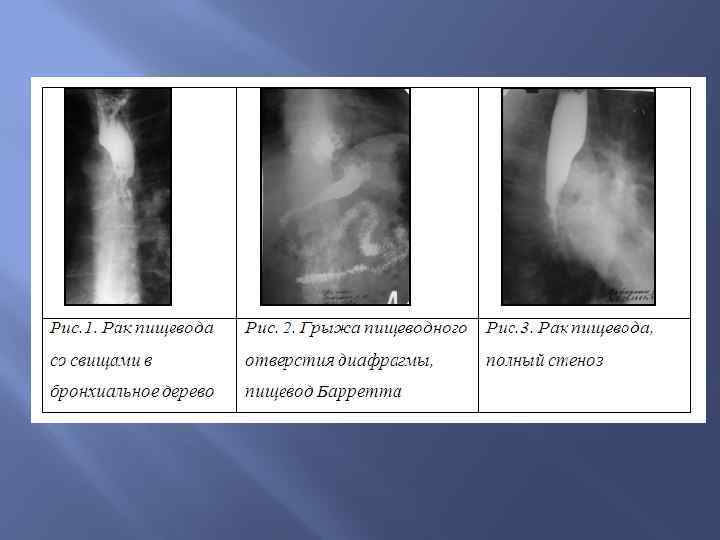

Развитие пищевода Пищевод развивается из переднего отдела первичной кишки. Аномалии развития пищевода 1) пищеводно-трахейные фистулы; 2) аплазия пищевода — отсутствие пищевода полное или частичное; 3) атрезия пищевода — полное или частичное отсутствие просвета пищевода, вместо него может быть сформирован фиброзно-мышечный тяж; 4) дивертикулы пищевода

Развитие пищевода Пищевод развивается из переднего отдела первичной кишки. Аномалии развития пищевода 1) пищеводно-трахейные фистулы; 2) аплазия пищевода — отсутствие пищевода полное или частичное; 3) атрезия пищевода — полное или частичное отсутствие просвета пищевода, вместо него может быть сформирован фиброзно-мышечный тяж; 4) дивертикулы пищевода